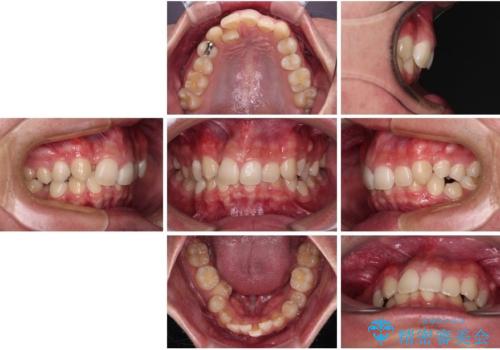

- 「前歯のデコボコが気になる」「前歯の中心がずれていて気になる」とご相談に来られた患者様の症例です。

診察の結果、上下の歯が並ぶためのスペースが不足しており、特に上顎右側の側切歯が内側(口蓋側)に転移していたため、正中が大きく右にずれている状態でした。

上下左右の第一小臼歯を抜歯してスペースを確保する計画を立てました。